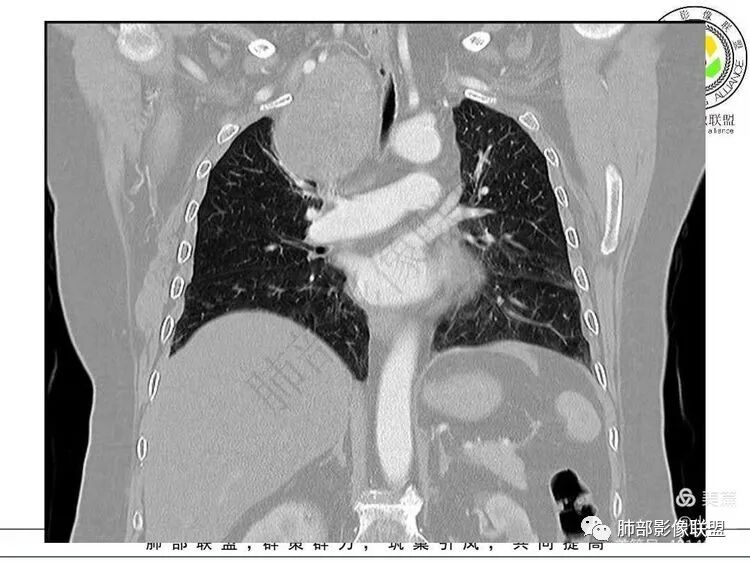

上腔静脉后上方

肺侧边缘光滑,D字征,肺血管受压外移肺外没问题

血管、压缩肺组织病灶的长轴:上下走形

推压血管,进入颈部

1. 右上胸廓入口区类椭圆形块影,边界清楚光整,纵向“嵌顿”于颈根部及上纵隔,向上推移右锁骨下动静脉,向外下方推移上肺胸膜及肺组织(肺血管、支气管),向前推移上腔静脉,界限清楚。